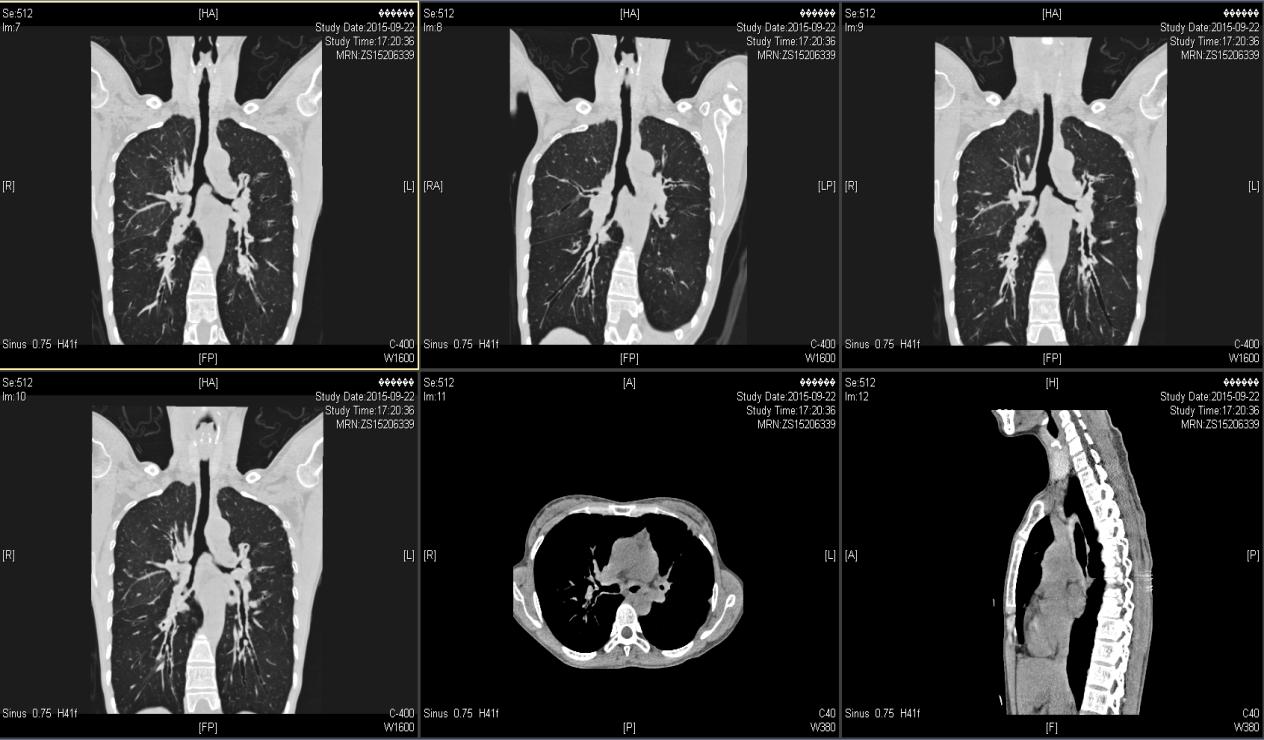

( 2015-9-22 ) 我院气管三维重建CT示 :气管、主支气管及其分支形态欠规则,管壁见明显增厚,管腔内壁凹凸欠光整,肺门处支气管管壁明显增厚,可见少许钙化,肺门处支气管管腔局部狭窄,远端分支管腔扩张呈囊柱状。见图1—图4。

图3

图4